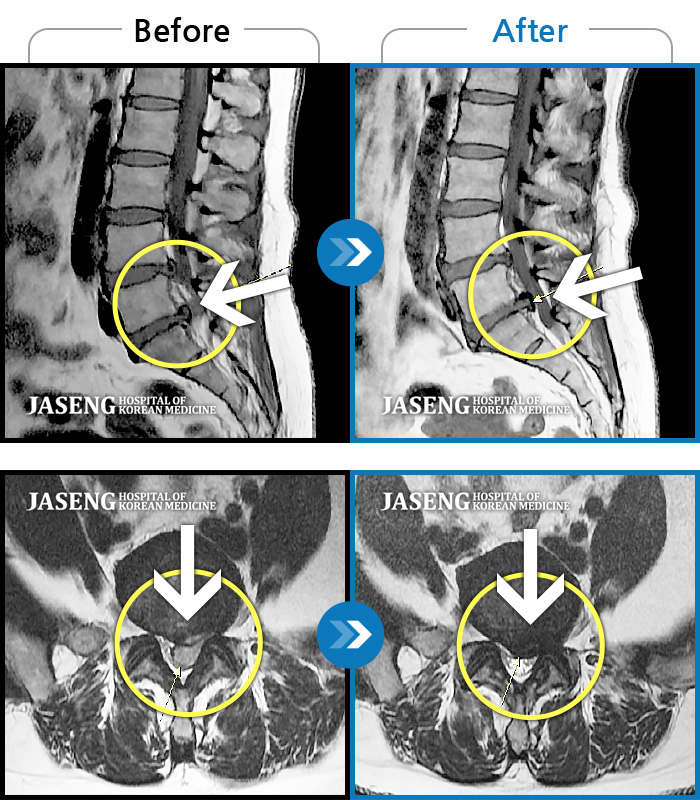

허리디스크

울산 · 정운석 원장

양측 하요추부 통증과 우측 하지 저림

촬영시기

2022.03.16 ~ 2022.11.12

2023.01.19